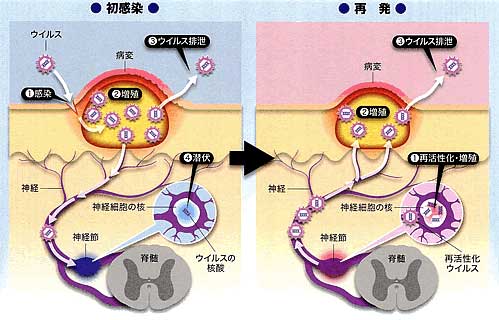

ヘルペス 山の手クリニック

丸善クリニック 性器ヘルペス ウイルス性